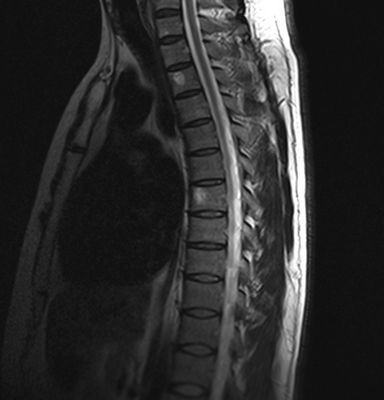

Гемангиомы на магнитно-резонансной томографии грудного отдела позвоночника (сагиттальная проекция, Т2 взвешенная последовательность)

МРТ позвоночника - высокоинформативный метод диагностики, использующий для построения детальных изображений структур области интереса свойства магнитного поля, радиоволны и компьютерную обработку. По показаниям исследование выполняют с контрастным усилением: в вену вводят препарат, содержащий хелаты гадолиния.

МРТ грудного отдела позвоночника (сагиттальная проекция, Т1 ВИ)

Магнитно-резонансные томограммы отображают внутренние структуры зоны интереса в трех плоскостях. Каждый снимок представляет собой один срез, на распечатанном фото МРТ их несколько.

В норме позвонки гладкие, повреждения отсутствуют. Фиброзно-хрящевые диски, выполняющие роль амортизаторов, не выпячиваются, имеют стандартную высоту, без признаков дегенерации. Спинной мозг выглядит на фото как белый шнур без видимых перекосов и других изменений.